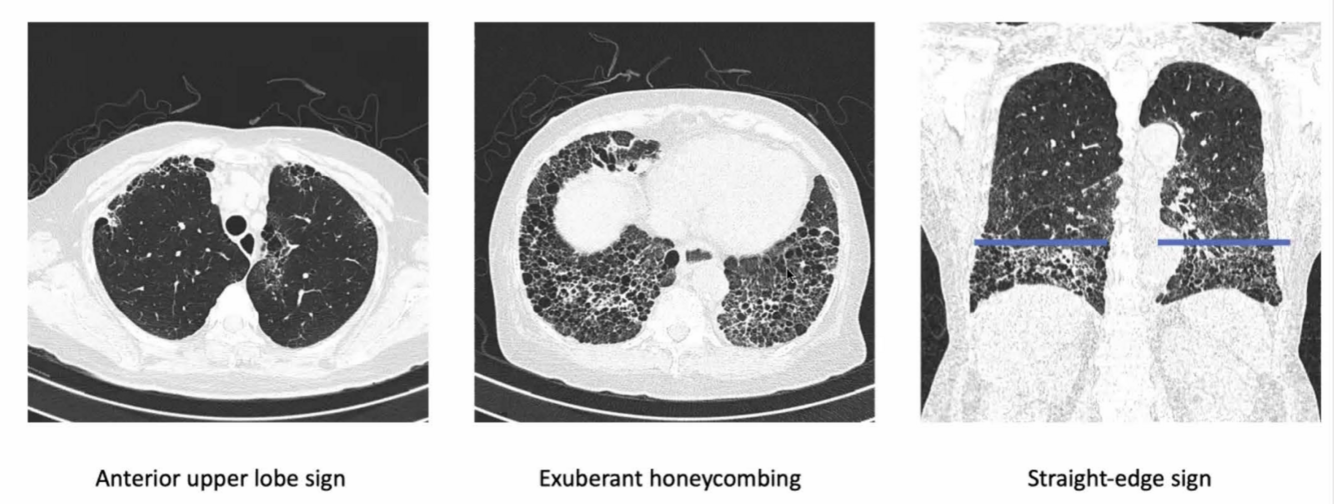

HRCT features suggestive of CTD-ILD

A

1) Anterior upper lobe sign

2) Exuberant honeycombing sign

3) Straight-edge sign

4) UIP pattern – honey combing & reticulation

5) NSIP pattern – GGO & reticulation

Common HRCT changes to specific ILDs:

RA: Usu UIP (honey combing & reticulation)

SSc: Usu NSIP (GGO & reticulation)

IIMs: overlapping NSIP and OP